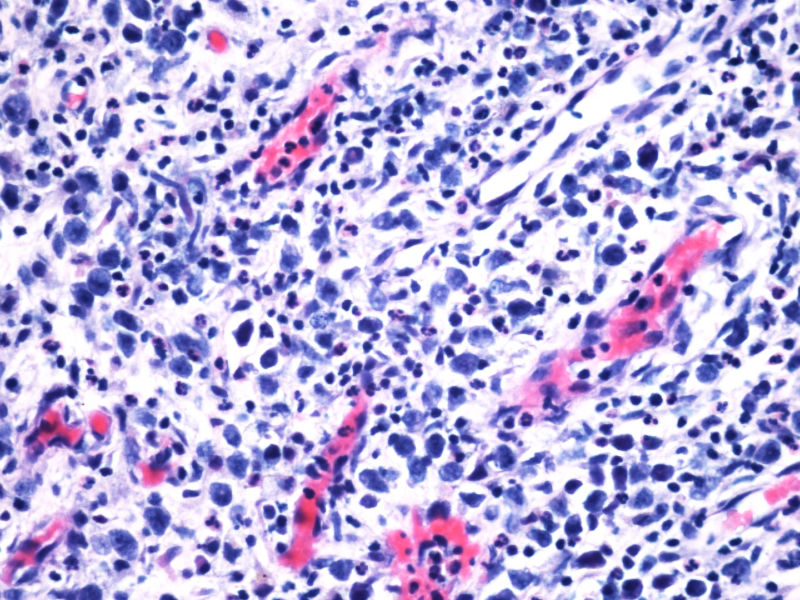

本例患者未查见淋巴结肿大,无肝脾肿大。其余标记物:大细胞显示CD2,CD3,CD4,CD8,CD5,EMA,TIA-1,GranB, oct, Bob1, EBER均阴性。

阳性的有CD30,CD15,CD43,ALK,perforin。

最终诊断为:ALK阳性的间变性大细胞淋巴瘤,淋巴组织细胞变异型。

本例全B,全T缺失,使诊断很困难,淋巴瘤范围内一般考虑①HL;②浆细胞分化的肿瘤如浆细胞骨髓瘤或浆母细胞瘤;③ALCL. 以下为鉴别:

1.关于CD15:可见于HL,偶尔(WHO: rarely)见于ALCL,甚至可意外地或异常地(WHO: exceptionally)见于外周T,非特指.

2.关于PAX5:应该是HL和ALCL鉴别非常好的标记。WHO: The B-cell nature of HRS cell is further demonstrable in approximately 95% of cases by their expression of the B-cell specific activator protein PAX5. 本例PAX5阴性,重点就只有放在ALCL上了。

3.关于CD43: 对比CD43和CD3的结果,并不能否认ALCL,甚至还提供了一个线索就是CD3- 是由于肿瘤细胞“改头换面”缺失表达造成的,如果追加CD2,4,5等可能就会使肿瘤“原形毕露”了。

最后,ALK+可证实以上的推断。